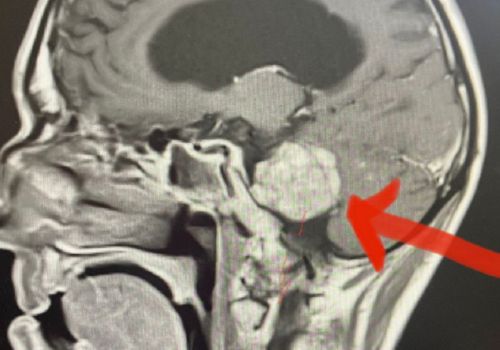

Оба пациента —молодые мужчина и женщина — оказались в стационаре практически одновременно, но с разными симптомами. Девушка с жалобами на потерю слуха долго лечилась у оториноларинголога, затем у невролога, пока не оказалась в больнице с подозрением на инсульт. Мужчину «скорая» доставила с жалобами на сильные головные боли и потерю координации. У обоих МРТ показало наличие опухоли — невриномы

По сообщению омского Минздрава, невринома — доброкачественное образование, возникающее из оболочки нервного ствола. Становится причиной раздражения и дисфункции пораженного нерва, компрессии прилегающих тканей. Отличается медленным развитием симптоматики и может долго оставаться незамеченной.

— Невринома головного мозга сама по себе опасности не представляет, однако по мере увеличения ее размеров происходит сдавливание прилегающих структур мозга. Рост опухоли может происходить как в сторону слухового прохода, так и в направлении мостомозжечкового угла, — рассказал заведующий отделением нейрохирургии БСМП№?1, к. м. н. Ярослав Шестериков.

Пациенты были прооперированы при помощи хирургического микроскопа с нейронавигацией. Врачи провели резекцию опухоли с минимальным повреждением структур мозга. Оба пациента после лечения полностью восстановились и благополучно выписаны домой